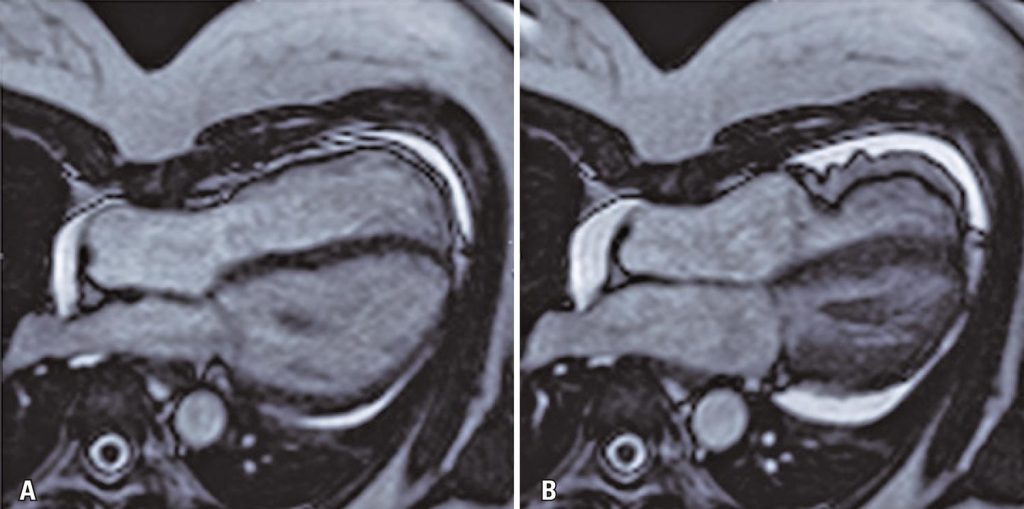

Cardiac magnetic resonance imaging was performed for proper evaluation of the right ventricle. Cardiac magnetic resonance showed normal biventricular function; however, tricuspid valve prolapse and tricuspid annulus disjunction were observed (maximum separation between the tricuspid valve and the free wall of the right ventricle was 5mm) ( ), along with pectus excavatum and mild pericardial effusion. Late gadolinium enhancement sequences revealed non-myocardial fibrosis ( ).